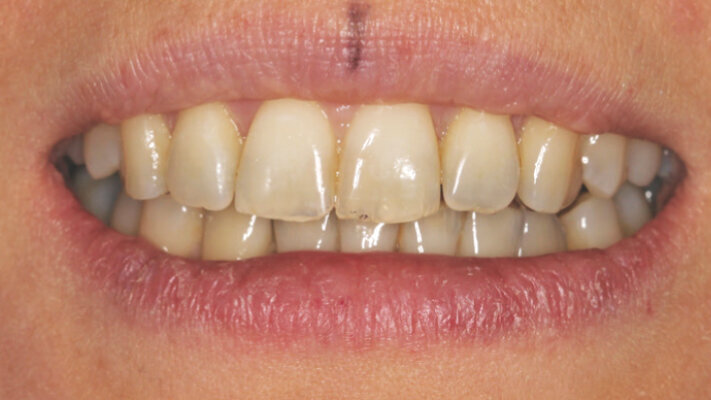

Pacientka navštívila naši praxi kvůli kloubním problémům – stěžovala si na obtíže v pravém TMK. Při intraorálním vyšetření jsme diagnostikovali II. třídu dle Anglea na levé straně, která se zhoršovala během dorazové fáze, mírnou mandibulární asymetrii s posunem dolní středové čáry zatímco horní střední čára korespondovala s filtrem, absenci 36, gingivální recesy nahoře i dole, stěsnání a klikání v kloubu (obrázky 1a–c).

Při extraorálním vyšetření byla zjevná hypoplazie zygomatických kostí, tupý nasolabiální úhel, dásňový úsměv 1 mm a mandibulární distookluze (obr. 2a–f).

Pacientka chtěla být operována co nejdříve z kosmetických důvodů kvůli zhoršující se distookluzi dolní čelisti. K té docházelo, protože mandibula setrvávala v centrickém vztahu, a proto byl naplánován časný chirurgický zákrok. Předoperační fotodokumentaci můžete vidět na obrázcích 9a–j a 10a–g.